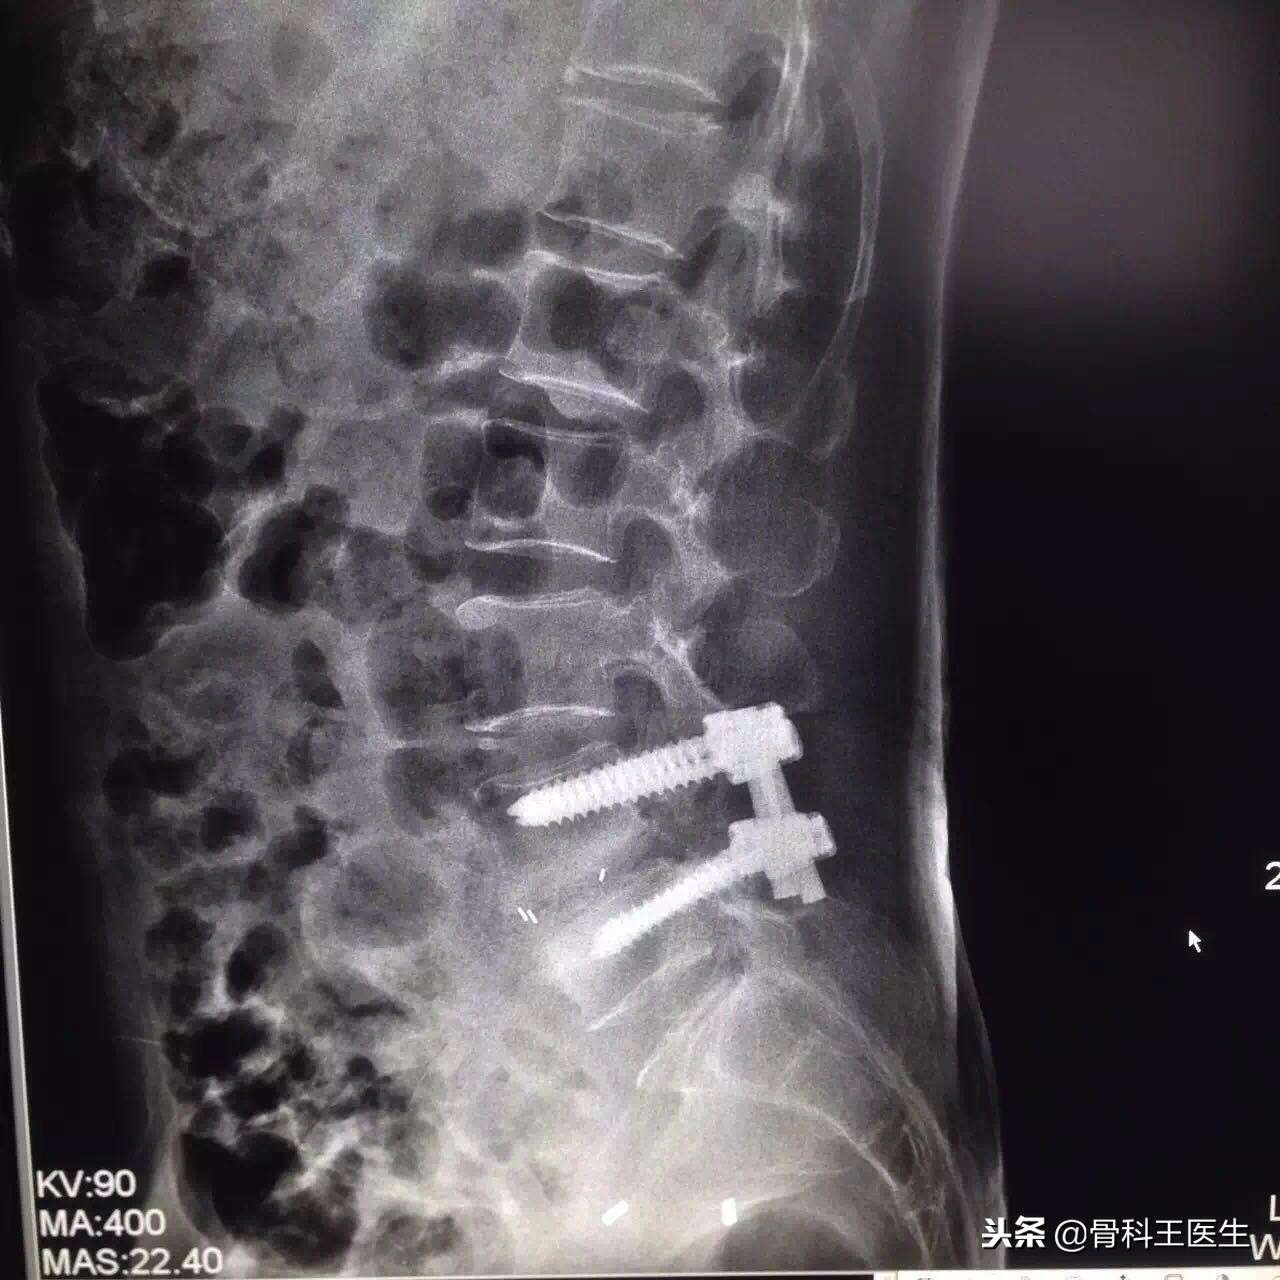

通常退变性的腰椎滑脱我们需要进行复位后减压融合固定手术,目前没有第二种手术方法,顶多微创进行而已。

腰椎滑脱